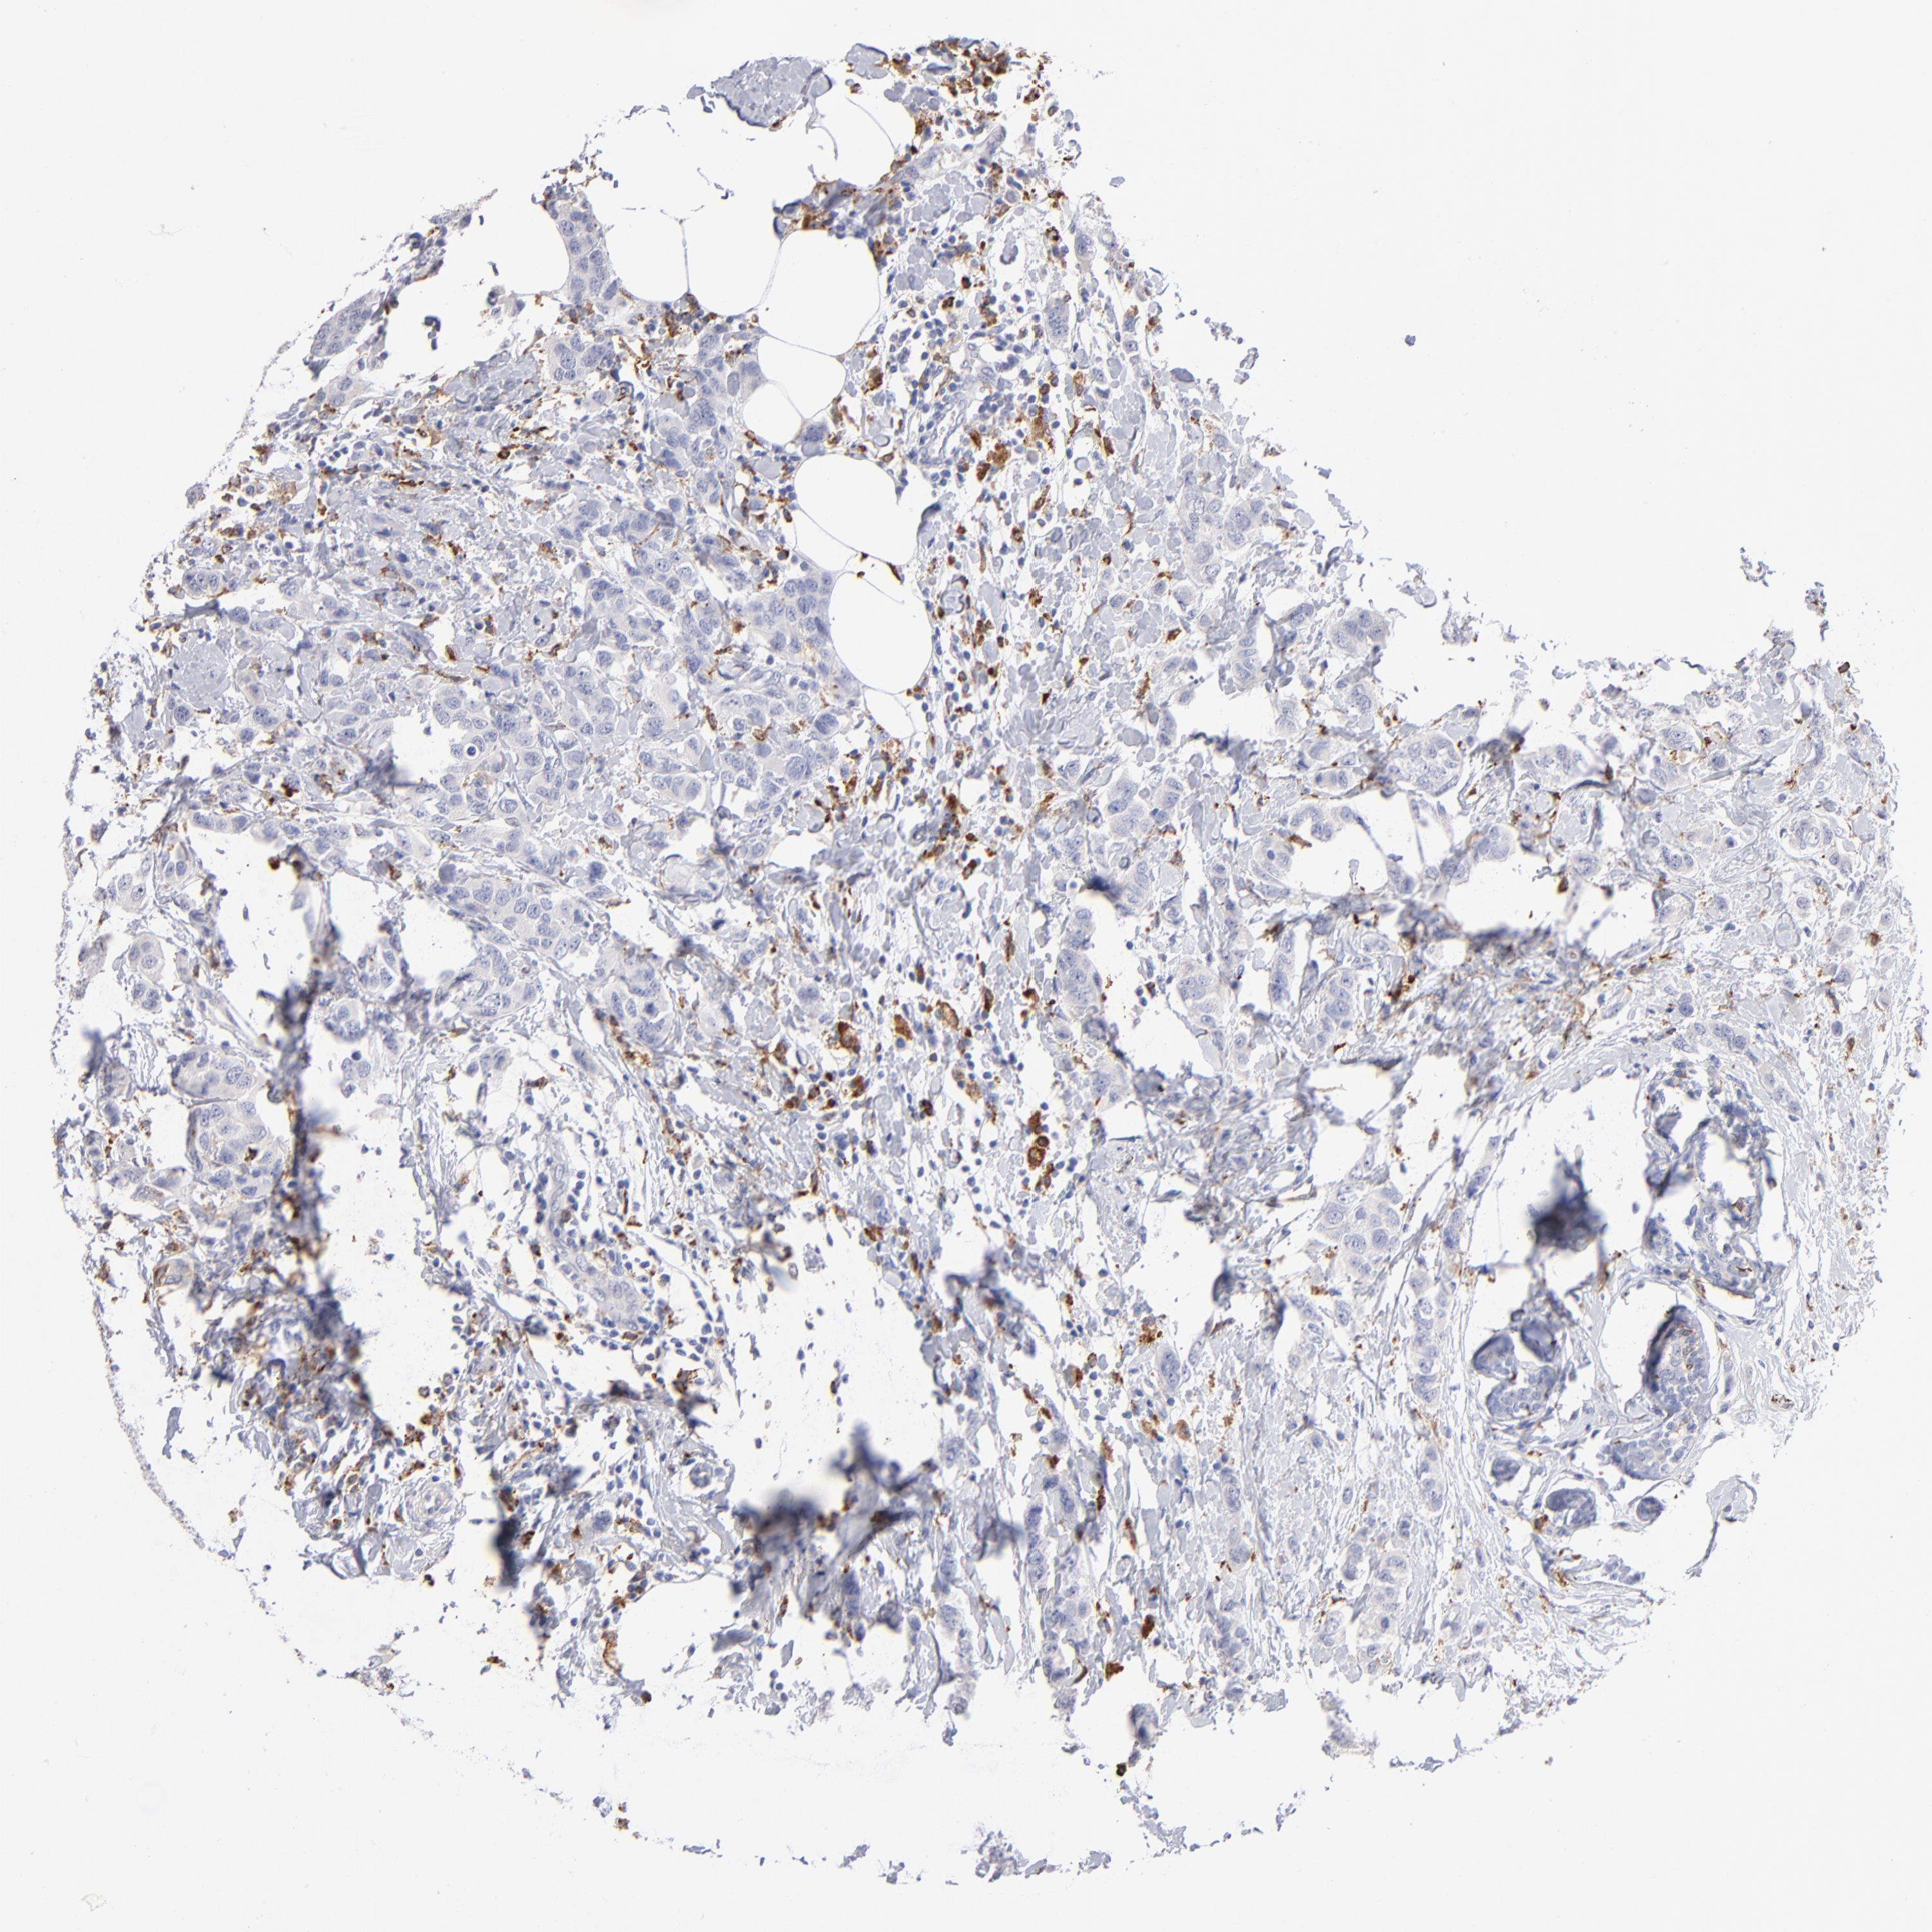

CANCER BREAST CANCER Show tissue menu

BRCA TCGA BRCA VALIDATION PROTEIN EXPRESSION

ANTIBODIES

AND

VALIDATION